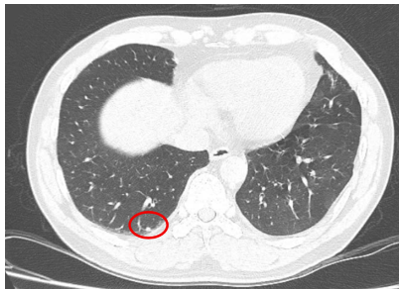

- Chụp cắt lớp vi tính ngực(11/07/2025) – trước phẫu thuật:

Hình 3: Hình ảnh chụp cắt lớp vi tính lồng ngực: Hình ảnh các nốt đặc rải rác 2 bên phổi, nốt lớn nhất kích thước 4mm (vòng tròn đỏ).